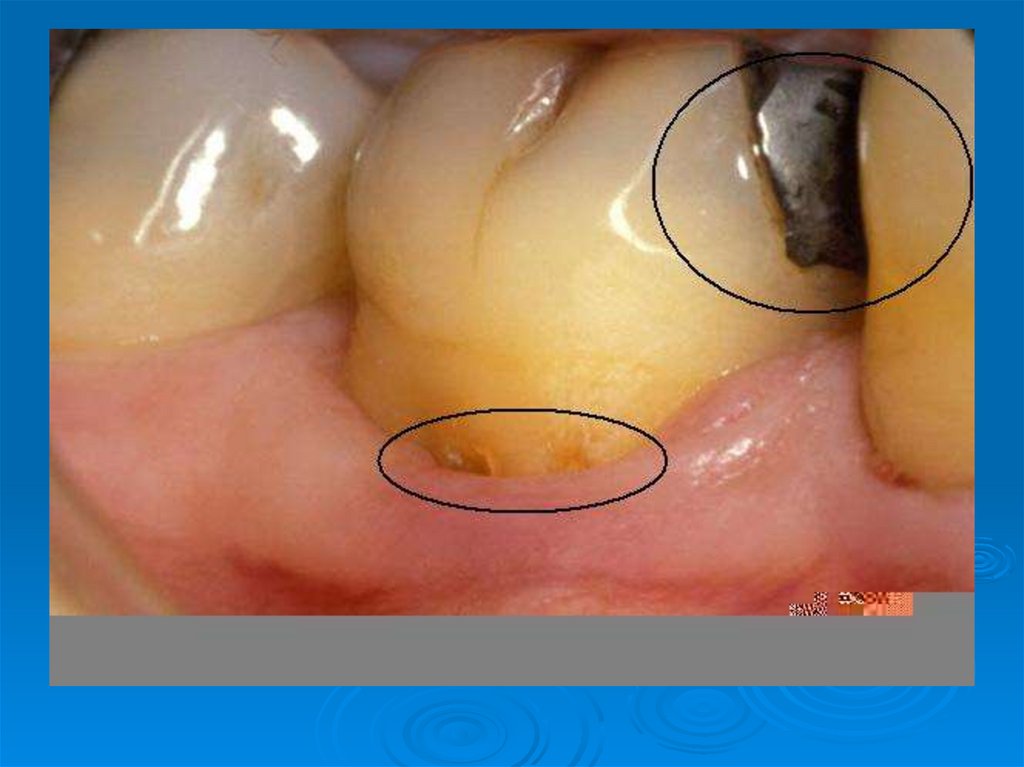

Клинические симптомы кариесогенной ситуации: плохое состояние гигиены полости рта, обильный зубной налет и зубной камень,

Наличие мягких (мягкий зубной налёт) и обызвествленных (твердый зубной налет – зубной камень)зубных отложений в большой степени

10. Клинические симптомы кариесогенной ситуации: плохое состояние гигиены полости рта, обильный зубной налет и зубной камень,

наличие множественных

меловидных кариозных пятен,

кровоточивость десен.

24. Наличие мягких (мягкий зубной налёт) и обызвествленных (твердый зубной налет – зубной камень)зубных отложений в большой степени

зависит от

качества гигиенического ухода

за полостью рта и зубами.